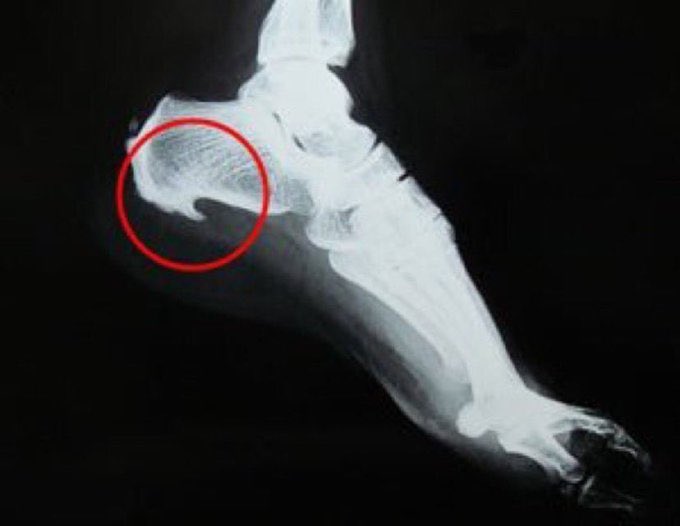

#شوكة_القدم

♦️عبارة عن التهابات في الأنسجة الرخوية،

يحدث بعدها ترسب للكالسيوم ليكون هذه الشوكة

♦️وهي استجابة الجسم للتوتر والضغط الواقعين على أربطة وأوتار القدم

♦️مثال:

عندما تصاب بالتهاب اللفافة الأخمصية ،

يستجيب جسمك للإجهاد عن طريق خلق نتوء في الكعب

و اللي تكون الشوكة